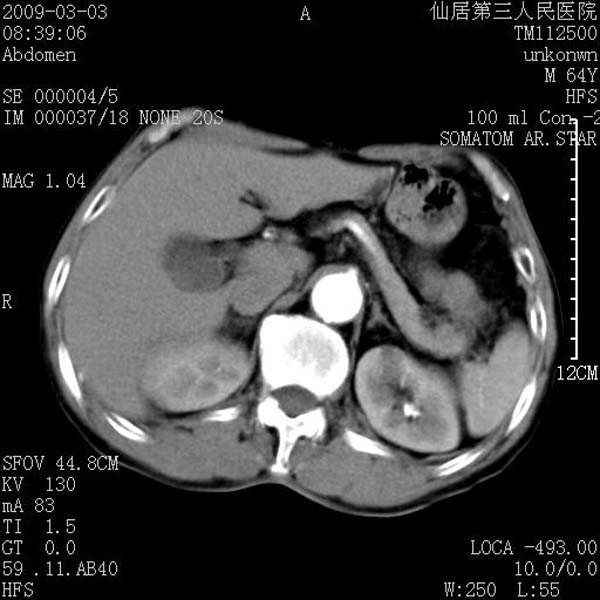

标题: CT18469:男性,64y,体检B超示肝脏低回声肿块,有胃溃疡手术 [打印本页]

患者,男性,64y,体检b超示肝脏低回声肿块,有胃溃疡手术史。

考虑----胃肠道间质瘤可能性大

从平扫及增强的特点来看,支持肝脏腺瘤并出血。

考虑胃间质瘤可能性大。

ct值呢?感觉没强化,象囊性。

考虑肝囊肿并出血可能性大.

考虑高密度囊肿可能性大